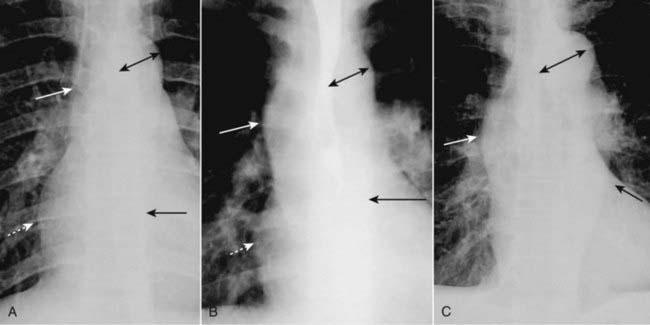

Figure 9-7 Appearances of the aorta.

A, Normal. The ascending aorta is a low-density, almost straight edge (solid white arrow) and does not project beyond the right heart border (dotted white arrow). The aortic knob is not enlarged (double arrow), and the descending aorta (solid black arrow) almost disappears with the shadow of the thoracic spine. B, Aortic stenosis. The ascending aorta is abnormal as it projects convex outward (solid white arrow) almost as far as the right heart border (dotted white arrow). This is due to poststenotic dilatation. The aortic knob (double arrow) and descending aorta (solid black arrow) remain normal. C, Hypertension. Both the ascending (solid white arrow) and descending aorta (solid black arrow) project too far to the right and left, respectively. The aortic knob is enlarged (double arrow).